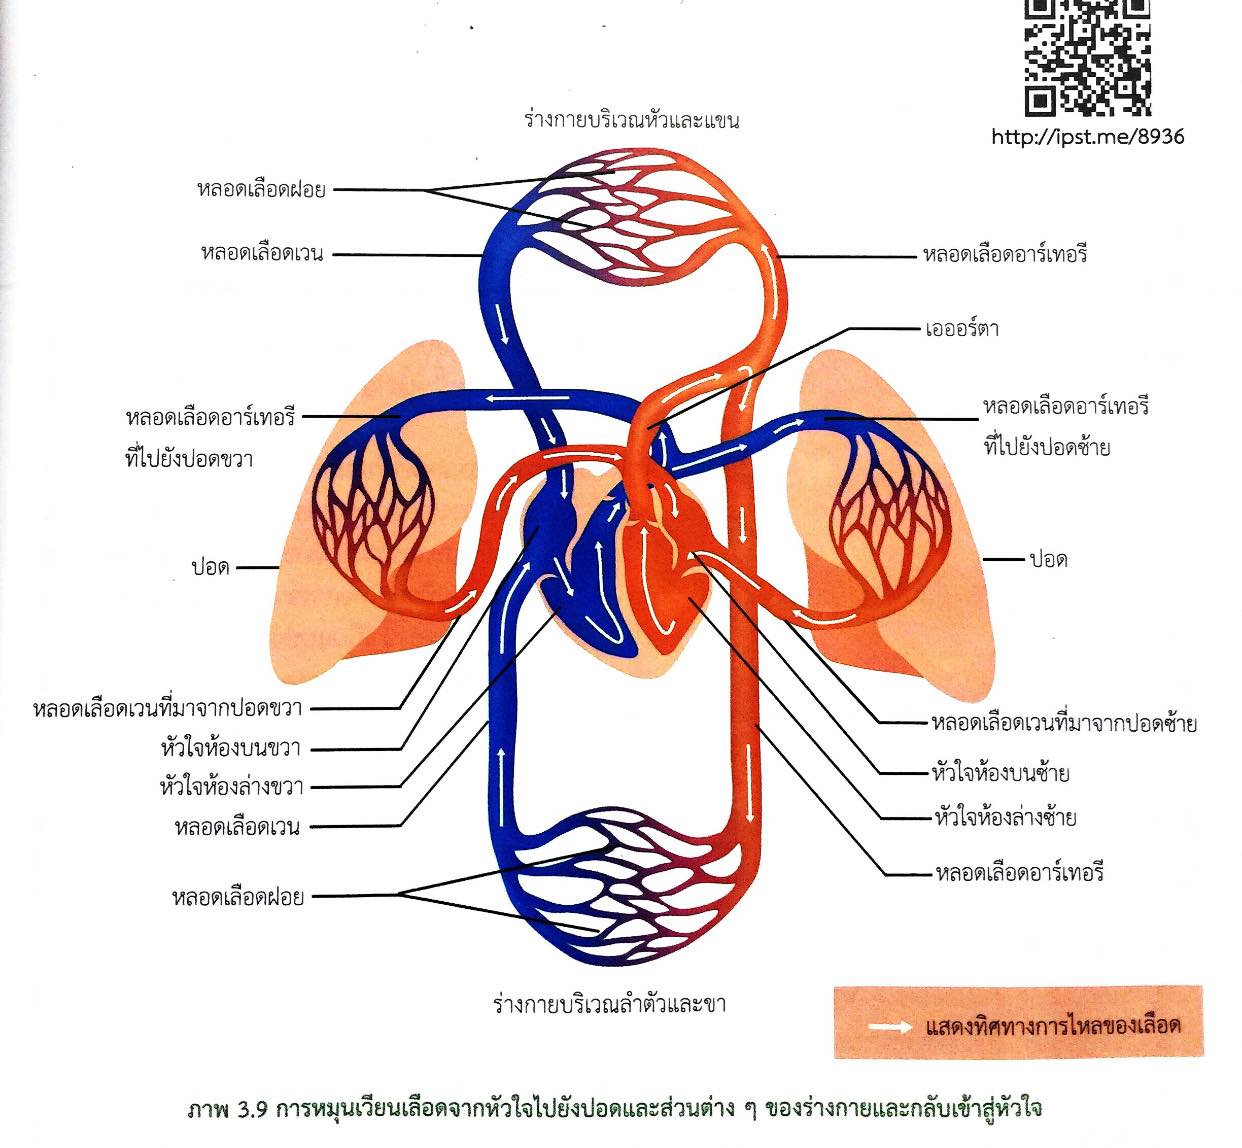

รูประบบไหลเวียนโลหิต

ระบบไหลเวียนโลหิต ทำหน้าที่อะไร และมีส่วนประกอบสำคัญอะไรบ้าง

37,900+ การไหลเวียนของเลือด ภาพถ่ายสต็อก รูปภาพ และภาพปลอดค่าลิขสิทธิ์ … หัวใจกับการไหลเวียนของเลือด – ระบบไหลเวียนโลหิต

หัวใจกับการไหลเวียนของเลือด – ระบบไหลเวียนโลหิต ม.2 ระบบหมุนเวียนเลือด | Science – Quizizz

ม.2 ระบบหมุนเวียนเลือด | Science – Quizizz ระบบไหลเวียนเลือด: หัวใจ

ระบบหมุนเวียนโลหิต 📝โน๊ตสรุประบบหมุนเวียนเลือด… – สภาติวเตอร์ By TS Council | Facebook